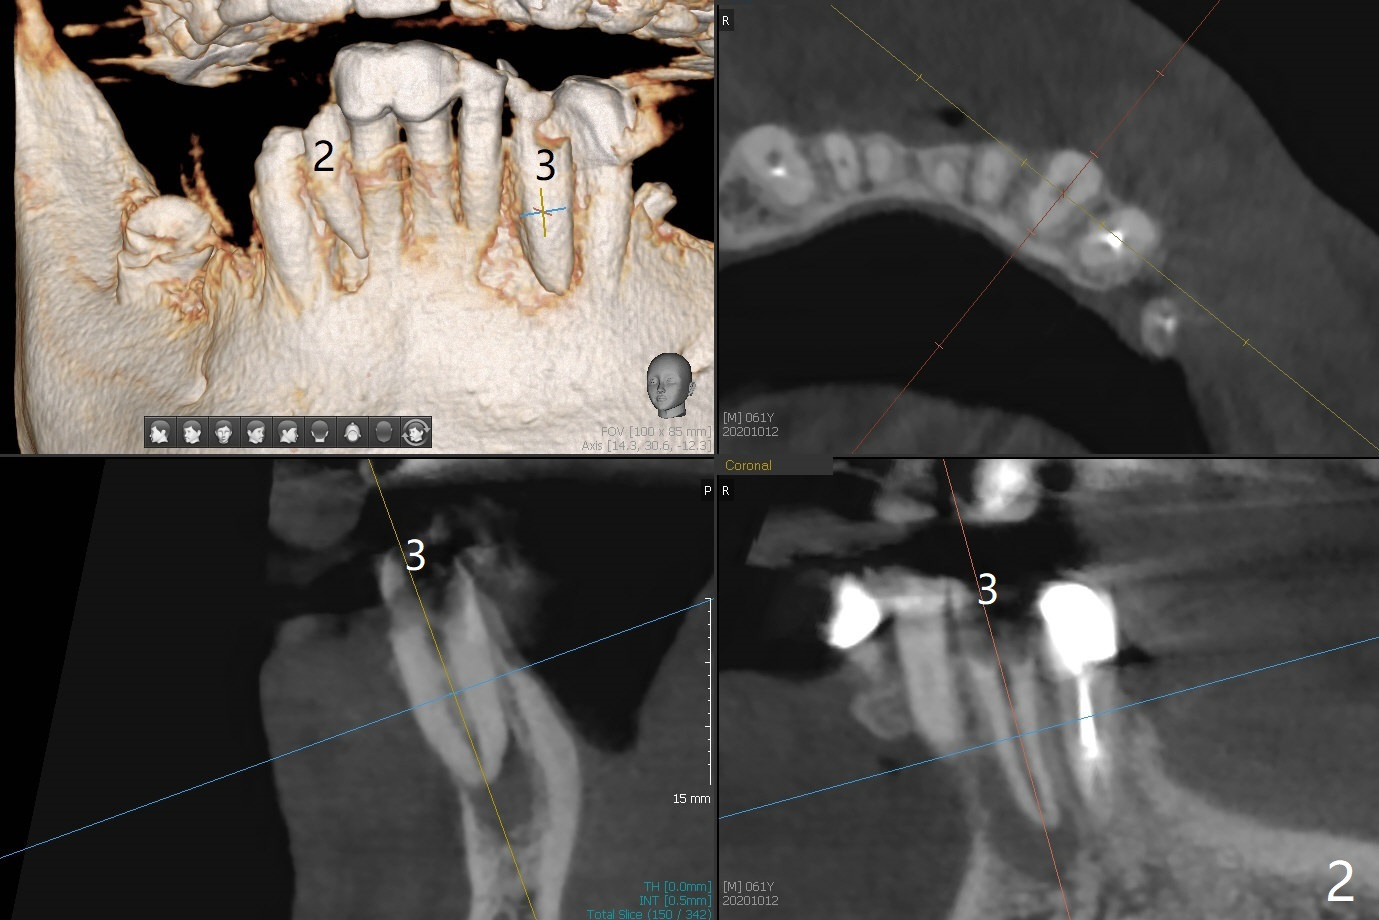

61男牙齿不好,左上4-8牙桥松动(图一,五,六),右下2,左下3根尖瘘道(图二),左上4,8也需要根管治疗,以上牙齿以及右下3插入球状牙桩(图一:*),然后在右上,左下,右下7植牙,放置球状基台(图一:箭头),固定上下活动义齿(覆盖义齿)。下前牙颊侧骨板几乎没有(图七)。左下7骨头(图八)宽于左下5(图三)。